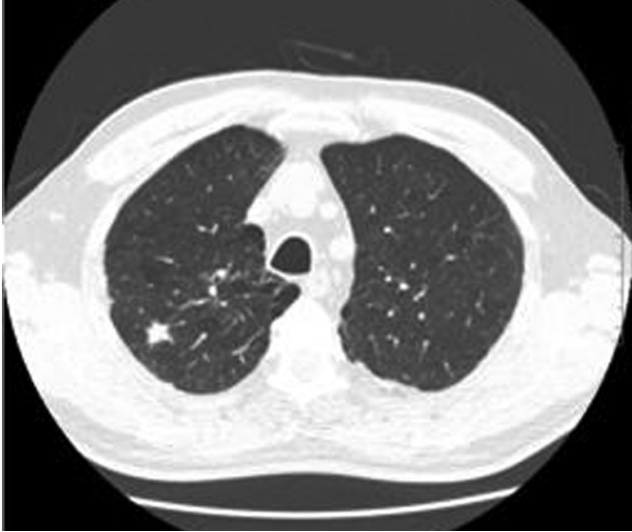

Das LMU Klinikum bietet Ihnen als Patient*innen und Zuweiser*innen mit seinem Lungenkrebs-Screening Programm eine strukturierte und neue Möglichkeit zur Krebsfrüherkennung. Mit einer speziellen, strahlenarmen Computertomographie (Low-Dose-CT) können selbst kleine Veränderungen in der Lunge erkannt werden, noch lange bevor Beschwerden auftreten. So kann frühzeitig und gezielt eine Abklärung und ggf. auch eine Therapie eingeleitet werden. Das Angebot richtet sich primär an all jene Menschen in unserer Bevölkerung, die durch Rauchen zur Risikogruppe gehören.

Rundherd

Lungenkrebs wird zumeist spät entdeckt – und dann ist eine Heilung oft nicht mehr möglich. Mehrere große internationale Studien konnten zeigen, dass eine strukturierte Früherkennung mittels Niedrig-Dosis-Computertomographie für Personen mit hohem Risiko (strake Raucher) die Lungenkrebsspezifische Sterblichkeit um etwa 20% senken kann. Basierend auf diesen Erkenntnissen wurde im April 2026 die Lungenkrebsfrüherkennung mittels Niedrig-Dosis-CT in den Leistungskatalog der gesetzlichen Krankenkassen aufgenommen. D.h. die Kosten für das Screening übernehmen die Krankenkassen. Das Institut für Qualität und Wirtschaftlichkeit im Gesundheitswesen (IQWIG) sowie der gemeinsame Bundesausschuss (G-BA) empfehlen die Durchführung der Lungenkrebs-Früherkennung.

• Bei Vorliegen des relevanten Risikoprofils wird eine Niedrig-Dosis-CT Untersuchung durchgeführt. Diese dauert nur wenige Minuten und benötigt kein Kontrastmittel.

• Die CT-Bilder werden von speziell geschulten Radiolog*innen sowie zusätzlich von einer KI-Software ausgewertet.